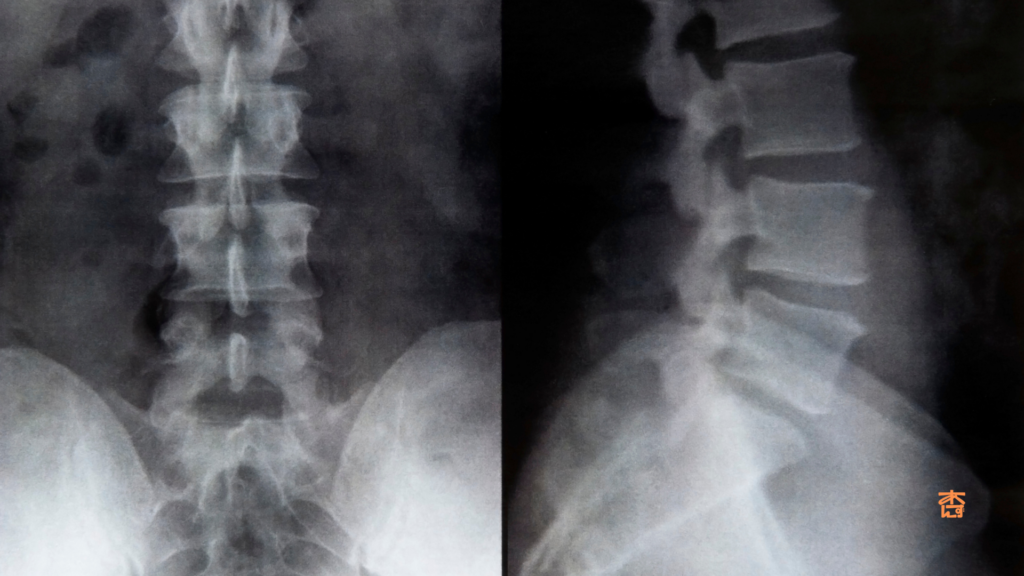

まずは専門機関での検査が大事です‼

また、レントゲン検査だけでは初期の腰椎分離症を見つけることが難しい場合があります。

より正確な診断のためには、MRI検査が有効だといわれています。